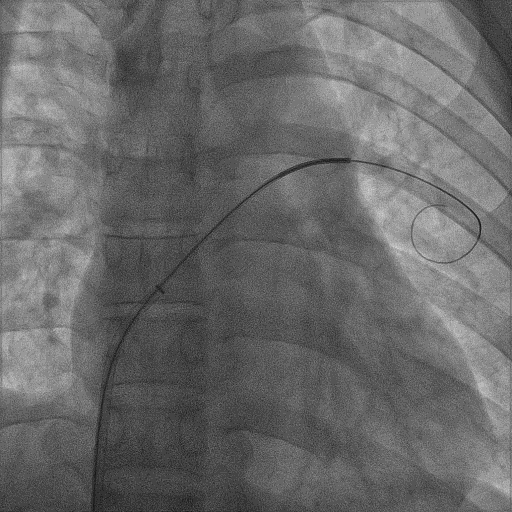

本例手術(shù)中,術(shù)者借助輸送鞘支撐,利用右心導(dǎo)管與導(dǎo)絲協(xié)作探尋卵圓窩邊緣孔隙。經(jīng)過多次細(xì)微調(diào)整與嘗試,對(duì)導(dǎo)管與導(dǎo)絲的角度和力度予以優(yōu)化,最終成功地讓導(dǎo)絲順利通過間隔,并將導(dǎo)管和導(dǎo)絲送達(dá)左上肺靜脈。

到達(dá)左上肺靜脈